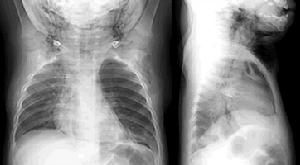

氣管、支氣管異物2.支氣管異物直接證象:不透X線的金屬異物在透視或照片中,可直接顯示異物的位置、形狀和大小。間接徵象:透X線及不透X線異物均可產生如下間接徵象:

(l)縱隔擺動:正常呼吸時,縱隔無左右擺動現象。支氣管異物時,一側支氣管發生部分性阻塞,呼、吸氣時兩側胸腔壓力失去平衡,使縱隔發生擺動。如為吸氣性活瓣阻塞,深吸氣時縱隔向患側移動,如為呼氣性活瓣阻塞,則呼氣時縱隔向健側移動。

(2)阻塞性肺氣腫:常與縱隔擺動時存在。表現為受阻塞的支氣管相應部位的肺透明度增高,肺紋理稀少,尤以呼氣時表現明顯。一側性肺氣腫說明異物位於患側主支氣管或其分叉處。如為肺葉性肺氣腫,可根據氣腫範圍確定異物位置。

(3)肺不張:為異物完全阻塞支氣管所致,表現為一側肺或某個肺葉、肺段的密度增高及體積縮小。